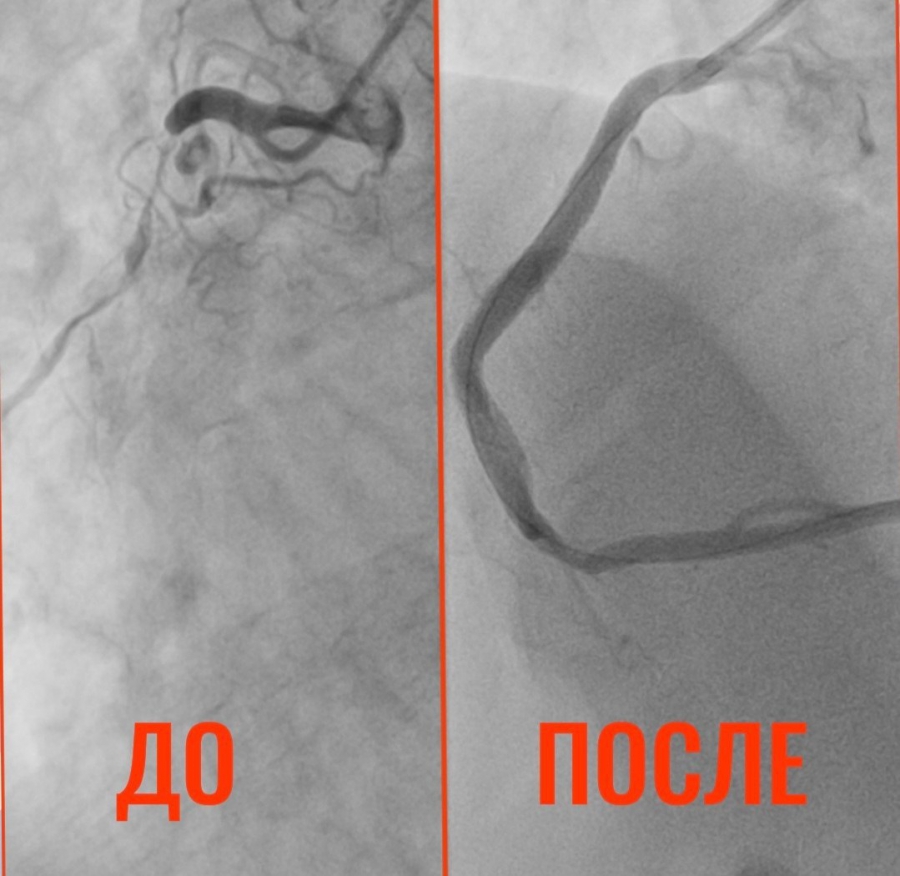

В Балакове Саратовской области спасли 32-летнего пациента с патологией сердца, которая свойственна для человека в глубокой старости. Об этом сообщает пресс-служба районной клинической больницы.

По данным медиков, житель Пугачева с 15 лет страдает гипертонической болезнью. Во время планового лечения он пожаловался на боли в сердце. В результате диагностики коронарных сосудов врачи оказались шокированы: кровь почти перестала поступать к сердцу. Состояние сосудов мужчины специалисты сравнили с изменениями, характерными для глубокой старости.

Пациенту провели операцию. Установлено три стента, кровоток восстановлен полностью. В данный момент его состояние стабильно.